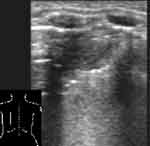

Плоская форма безвоздушного участка, когда в одном срезе он имеет размеры до нескольких см, а в перпендикулярной ему плоскости гораздо меньше, свидетельствует об ателектазе (Рис. 4, 5). При обширных безвоздушных участках на его присутствие указывает более острый конус безвоздушного сегмента, более высокое стояние края легкого, чем на противоположной стороне. В отличие от пневмонии в ателектазе не визуализируются эхогенные полоски содержащих воздух бронхов [7]. Исключение могут составлять крупные ателектазы у новорожденных, поскольку причина их возникновения не обструкция бронха, а нерасправление части легкого. Позади безвоздушных участков регистрируются усиленные эхосигналы.

[Увеличить]

Рис. 5. То же, что на Рис. 4, во взаимно перпендикулярной плоскости.